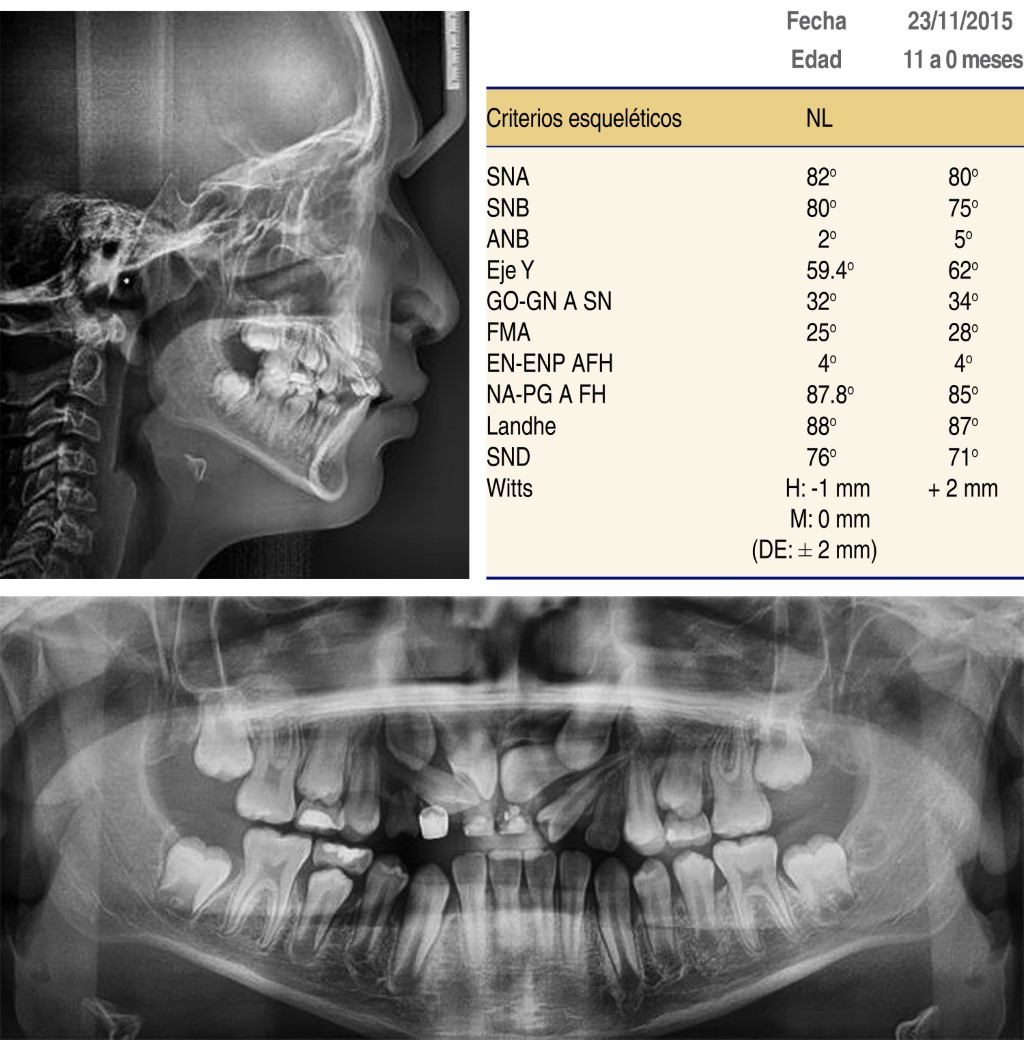

A pretreatment lateral radiograph showed (Figure 3). class II hyperdivergent skeletal pattern, and cephalometric measurements were obtained at onset. In the panoramic radiograph, we observed mixed dentition (37 teeth present, 8 deciduous and 29 permanent teeth). The following teeth were retained: upper left central incisor, upper right central incisor, upper lateral right incisor, and upper right and left canine